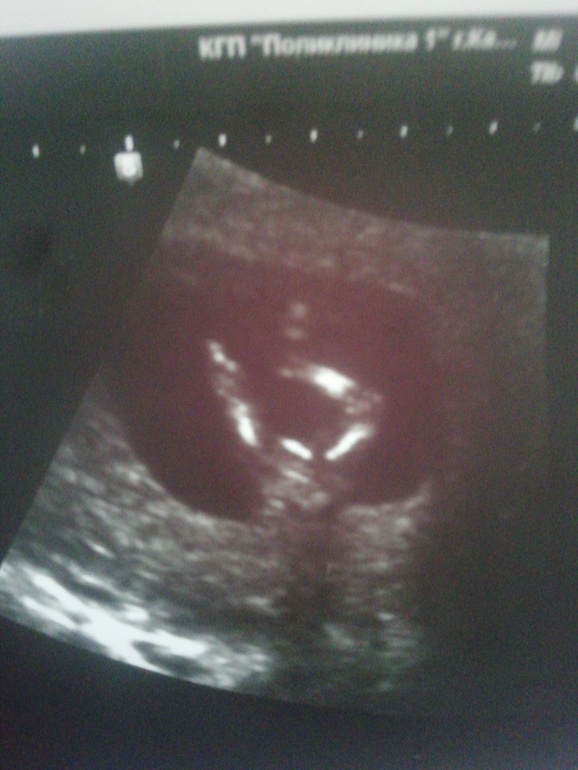

Бугорок как у моей козявочки. Девочка. А когда мсльчик он вверх больше торчит)))

По форме головки) Заметила, у кого мальчишки, такая. В любом случае желаю вам лёгкой беременности и здорового малыша или малышку!